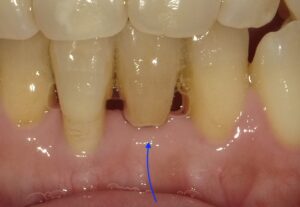

画像の矢印の歯が歯周病が進行し暫間固定で経過を見ていました。

周囲のホ根が完全になくなってしまいましたので

抜歯をし、その歯を接着剤でとめました。

矢印がその歯になります。

内側から見た状態です。実際歯があるように

見えます。